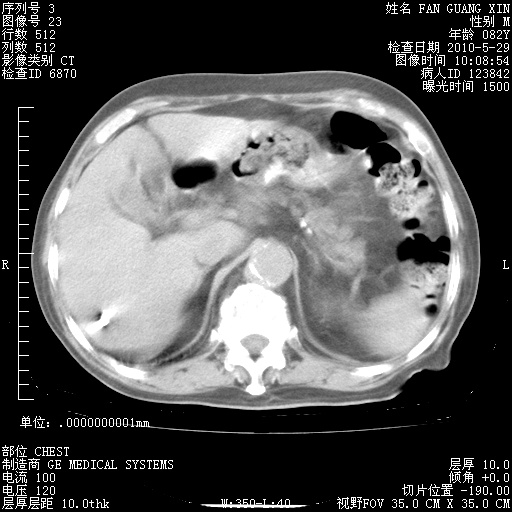

再治疗10天后的肺部CT

再治疗10天后的肺部CT 纵膈窗

阅读此次胸部CT,肺间质渗出性改变较入院时有吸收。目前从体温、白细胞、中性分叶明显增高,肯定存在细菌感染(发生医院感染哦,若无消化道及泌尿系统等感染的依据,肺部感染可能大)。若你院头孢哌酮舒巴坦钠耐药率较高,同意你的方案,若48小时体温仍高,可考虑使用碳青霉稀类抗菌药物,同时可予超声雾化、注意滴数时加大液体量。白蛋白33.30g/L较低哦,需加强营养等支持治疗。